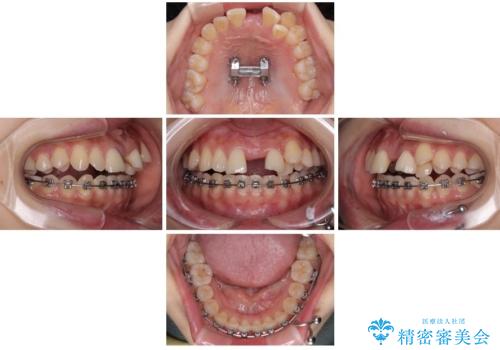

急速拡大装置 狭い上顎歯列を改善して、八重歯を改善した片側抜歯矯正治療

- 左上の前歯のがたつきを主訴に来院された患者様です。

上顎歯列が下顎の歯列に対して狭小であり、一部下顎の奥歯が上顎よりも外側に位置している状態でした。

上顎の歯列を拡大しスペースを設け、さらに左上の小臼歯を一本抜歯し左上の八重歯を歯列内に入れ整えていくことにしました。